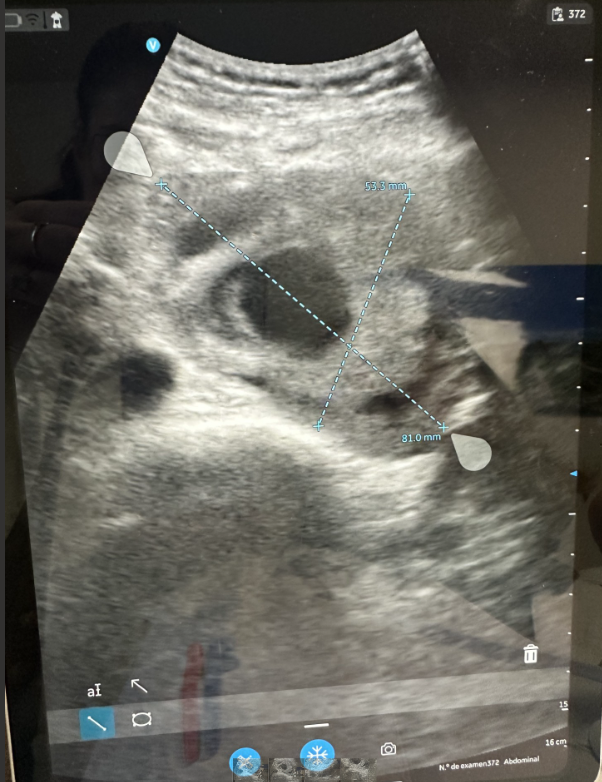

La ecografía clínica realizada en nuestra consulta de Atención Primaria mostró un aneurisma de aorta infrarrenal de 5,3 × 8,1 cm, con trombo intramural y sospecha de disección, hallazgo no presente en estudios previos.

Antecedentes de enfisema pulmonar, fumador activo, masa pulmonar cavitada en estudio, cáncer vesical tratado mediante RTU (2000), y apendicectomía. En agosto de 2024 se realizó un angio-TAC donde se identificó un aneurisma de aorta abdominal pararrenal, originado inmediatamente por debajo de la arteria renal izquierda y extendiéndose hasta 3 cm de la bifurcación aórtica, con diámetro máximo de 5,2 × 7,4 cm y trombo mural. El paciente rechazó la intervención quirúrgica propuesta tras ser informado de riesgos y alternativas.